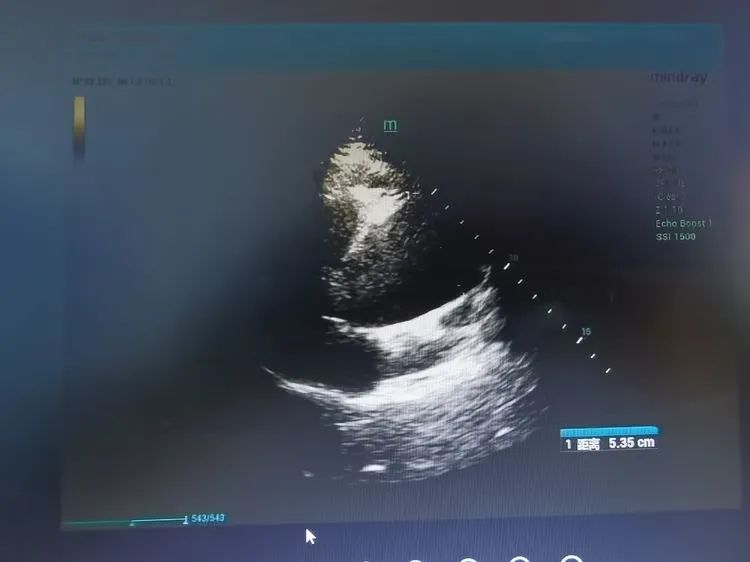

近日,今年82岁,家住谢家集的牛大爷突发胸痛,来不及多想,家人赶忙将其送至广济医院心内科。在东方医院集团垂直管理下,心内医疗中心李枫院长正在广济医院坐诊,李院长第一时间接诊,在心脏彩超检查的配合下,确诊牛大爷为升主动脉瘤样扩张,合并主动脉瓣狭窄。

在会诊时,心胸外科医疗中心朱胜院长明确表示:“患者升主动脉内径超过50mm具有明显的手术指征,如果老人升主动脉瘤继续发展,很可能会发生动脉瘤破裂、或者主动脉夹层,这是十分凶险的危急重症。”现在患者病情看似平稳,实则是命悬一线,一旦发病,基本必死无疑,能救治牛大爷的方法只有立刻进行“升主动脉置换术”。